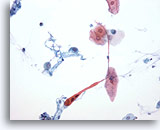

Figure 76

Sputum

Orangeophilic cells with hyperchromatic nuclei are suspicious for squamous cell carcinoma. 60x

Sputum

Orangeophilic cells with hyperchromatic nuclei are suspicious for squamous cell carcinoma. 60x

Figure 76

Sputum

Orangeophilic cells with hyperchromatic nuclei are suspicious for squamous cell carcinoma.

60x

Sputum

Orangeophilic cells with hyperchromatic nuclei are suspicious for squamous cell carcinoma.

60x